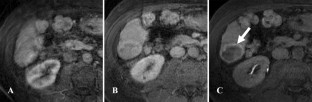

Fig. 3